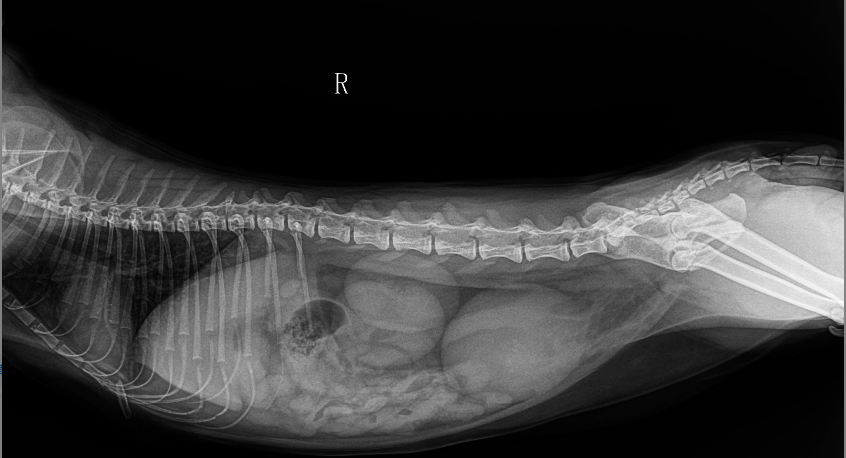

新手认清x线解剖,必先学会这9张正常猫咪的胸腹部x线片!

图片尺寸576x387